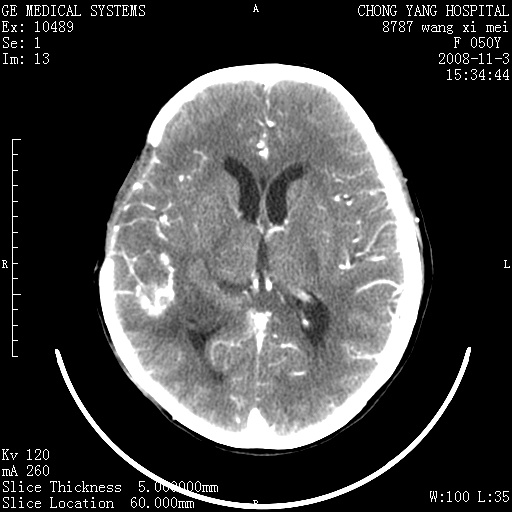

右侧颞顶部可见低密度实变影,内见不规则钙化灶,边界不清,占位效应明显,侧脑室后角受压移位,符合胶质瘤术后复发改变。

右颞骨局限性缺如,局部脑组织无外隆。右颞叶可见片状脑脊液样低密度影,边缘较清,右侧侧脑室三角区可见一块状等密度影,且伴有强化,余未见明显异常改变。

考虑:右大脑术后改变伴肿瘤复发。

手术后局部片状低密度改变(软化灶),其后方颞叶似等密度病灶,界限不清,内见钙化,有轻度占位效应,但增强后强化之血管走行如常。应不考虑:复发!